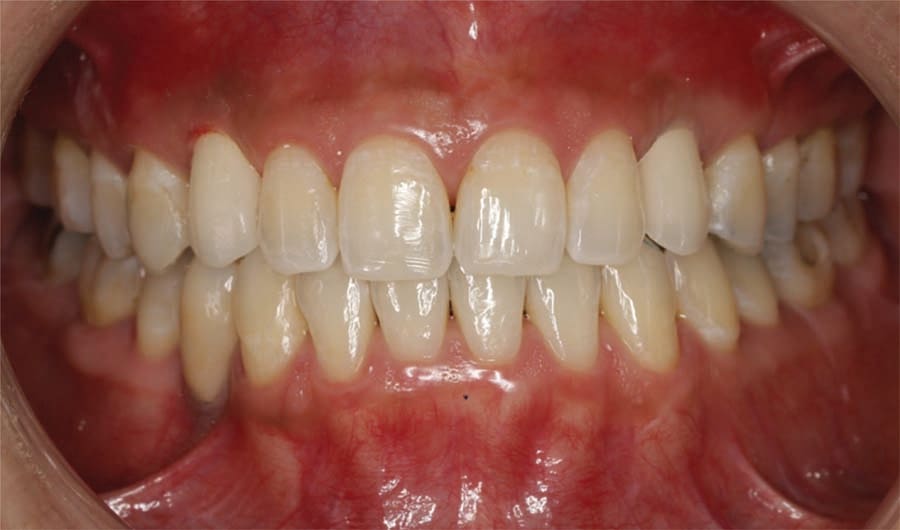

The patient returned and the provisional crowns were removed and cement cleaned from the abutments. The final crowns (lab processed from Jason J. Kim Dental Aesthetics) were tried in and margins checked with an instrument. The occlusion was checked and verified light occlusion was present on occlusion and there were no contacts in excursive movements. The crowns were cemented to the abutments with FujiCEM. Following setting of the cement marginal cement was cleaned with an instrument and a radiograph taken to confirm crown fit to the abutments and no residual cement subgingivally (Figure 20). The patient was given a mirror to evaluate the esthetics of her new smile and indicated she was happy with results, commenting it looked natural (Figure 21 through Figure 24). She was placed on regular 6-month prophy recall.

Treatment of over-retained deciduous teeth can pose complications in the esthetic zone to achieve a natural smile and meet patient expectations. As deciduous teeth are narrower in dimension than their permanent counterparts in the anterior, an orthodontic component is often necessary in the treatment plan to create sufficient mesial-distal space to accommodate a restoration that mimics a permanent tooth. Lack of development of a permanent anterior tooth, as in the case presented, leads to underdevelopment of the ridge facially, complicating implant placement to replace the deciduous tooth. Ridge grafting is required to widen the ridge to permit implant placement so that dehiscence does not result at placement or later under function. Hence, treatment planning these types of cases is a multi-procedural approach to achieve esthetic goals and create a natural smile.